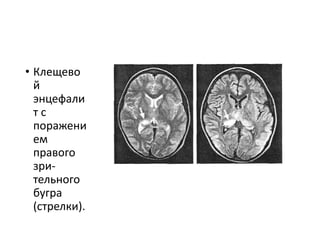

• Клещево

й

энцефали

т с

поражени

ем

правого

зри-

тельного

бугра

(стрелки).